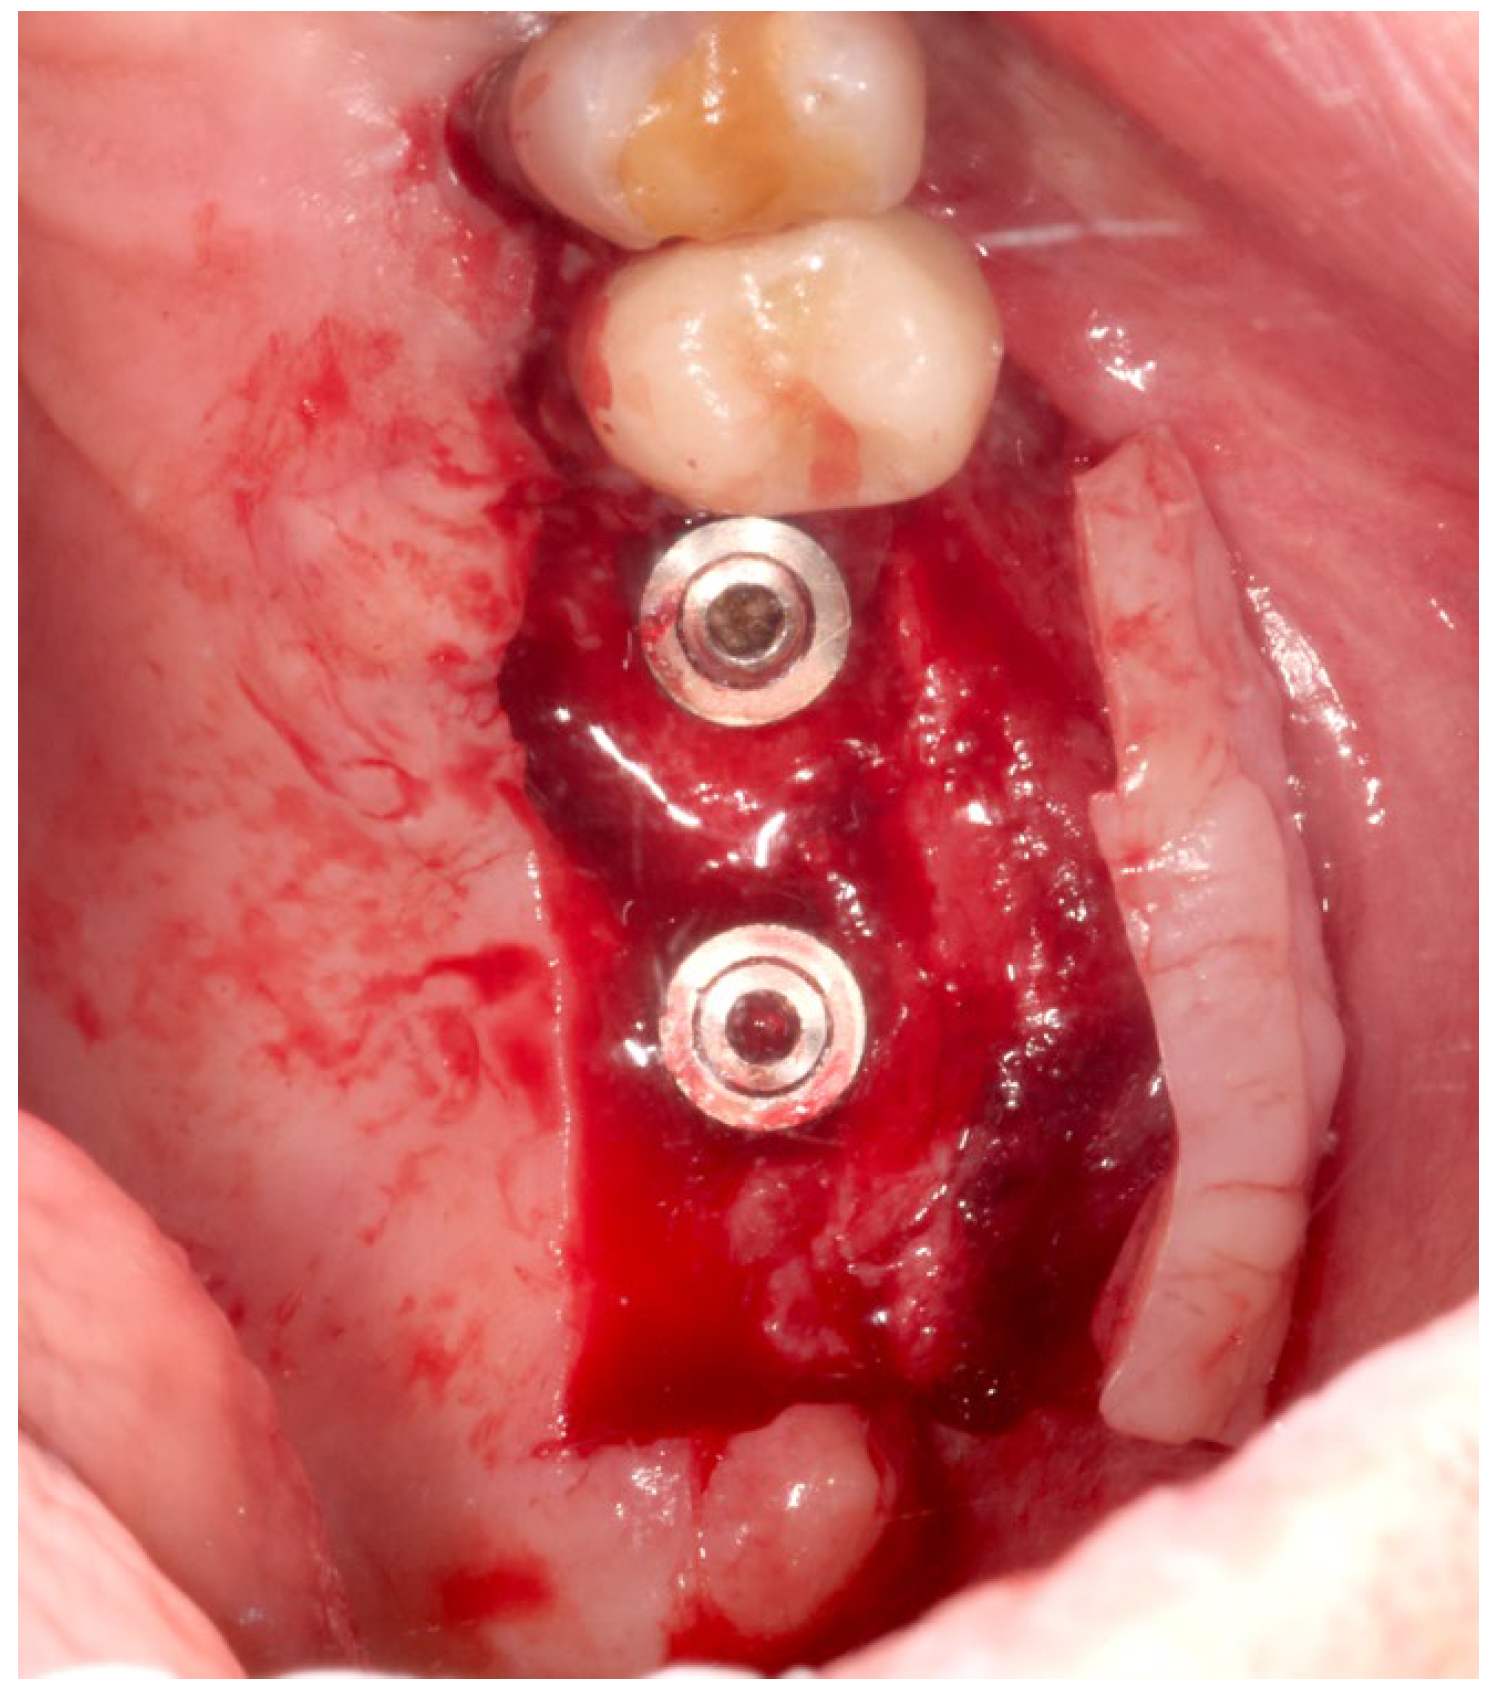

The same experienced surgeon (MS) operated on all patients. The surgical procedures were performed during the implant uncovering stage, 20 weeks after implant placement. Before surgery, the patient rinsed with a 0.2% chlorhexidine solution (Dentosan 0.20, Johnson & Johnson, Pomezia, Italy) for 1 min. Following local anesthesia with mepivacaine 2% (Mepivacaina Pierrel Pharma srl, Capua, Italy), two vertical incisions were made, on the buccal side, mesially and distally to the mucosa of the edentulous area covering the fixtures, extending five millimeters beyond the muco-gingival junction of the adjacent teeth. The incisions were continued on the palatal side of the edentulous area in such a way as to extend for 4 mm into the keratinized mucosa; the ends of the parallel incisions were connected by a further horizontal incision on the palatal side. Subsequently a partial-thickness flap was elevated from the palatal edge to beyond the muco-gingival junction on the buccal side using a 15-C blade (Hu-Friedy, Milan, Italy) (Figure 2). The connective tissue above the cover screws was removed with a curette, and the healing abutment was positioned after filling the internal part of the fixture with 1% chlorhexidine gel (Corsodyl gel®, GlaxoSmithKline Consumer Healthcare S.p.A., Baranzate, Italy) [16]. A double layer of L-PRF membrane was then applied to the palatal surgical wound (Figure 3) and stabilized by compressive sutures. The flap was positioned buccally using a 3-0 non-absorbable silk suture (Ethicon Perma-Hand, Johnson & Johnson Medical Spa, Pomezia, Italy) fixed to the periosteum.

Figure 2.

A partial-thickness flap was elevated to uncover the implants.